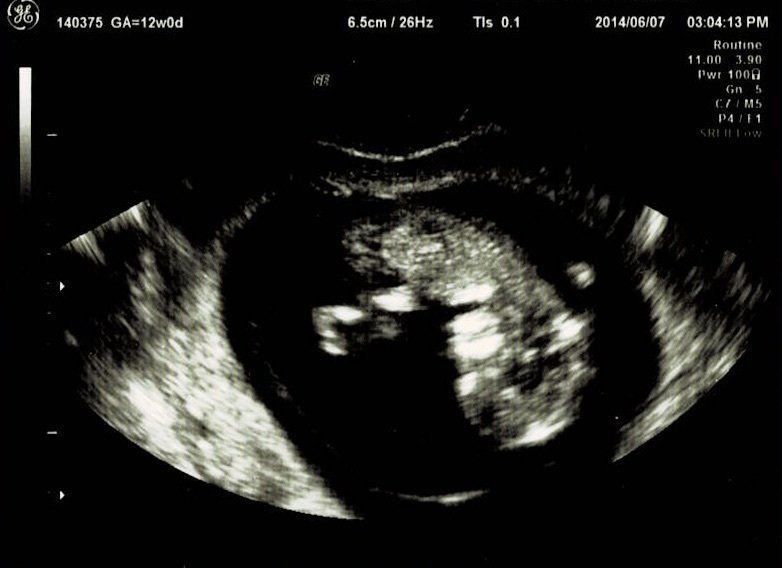

妊娠12週目エコー写真

つわり真っ盛り。しかし、おなかはまだ大きくありません。この日は採血をして、麻疹、風疹などの抗体があるか、梅毒の反応がないかなどの妊娠前期検査をしてもらいました。赤ちゃんはきちんと手足が見えて驚きました。さらには背骨まで確認できました。改めておなかの中に人間がいるという感慨がわいて、不思議な気持ちに。ガイコツみたいなエコーでもかわいいと感じました。

この日は、BPD(頭の左右幅)、AC(おなかの周りの長さ)、FL(太ももの骨の長さ)を測って、赤ちゃんの育ちぐあいを見てくれました。このエコーは足の骨を測っているところです。足の指らしき骨も見えます。先生がスムーズに赤ちゃんの頭やおなか、足を探すのが面白く、測っている最中のエコーもずっと眺めていました。